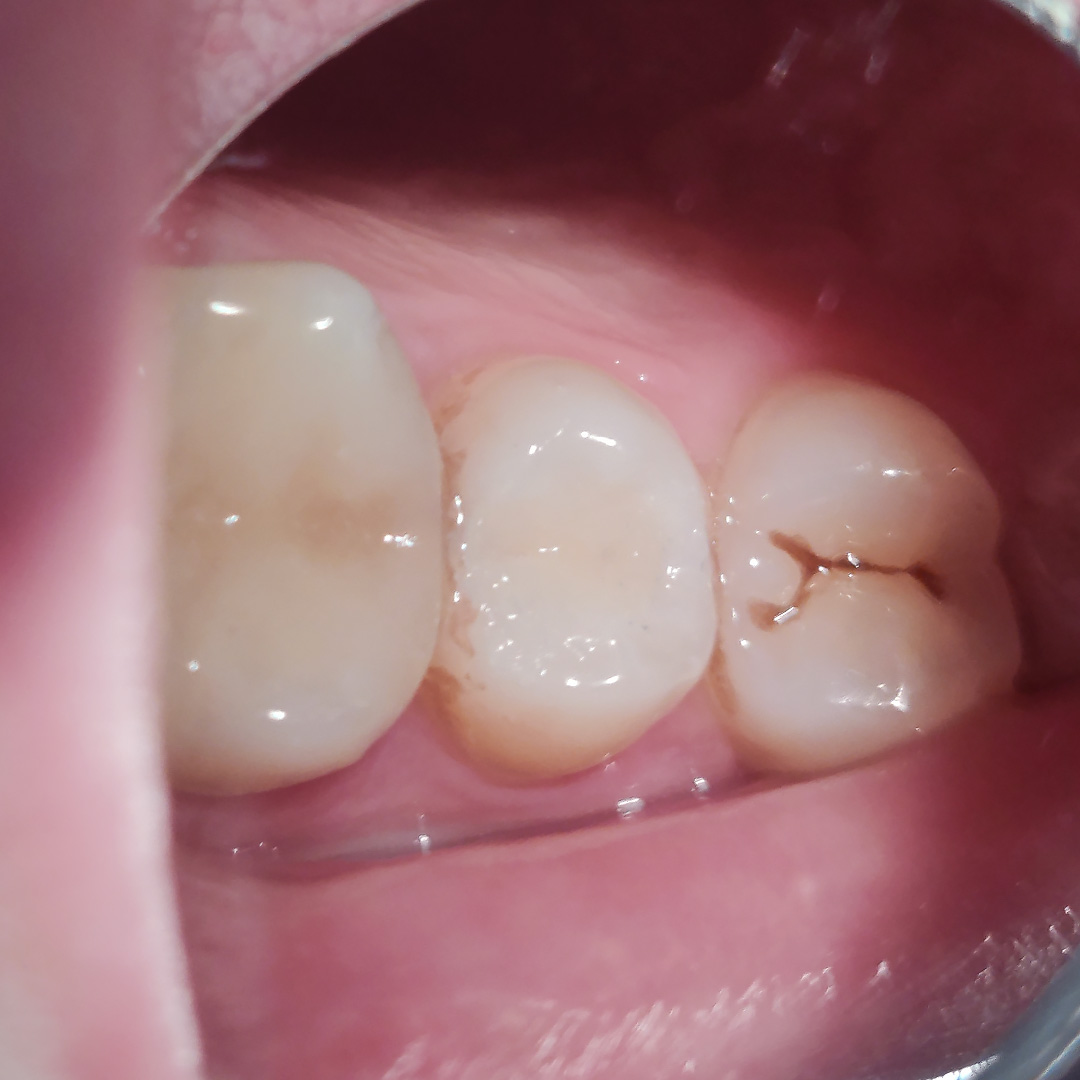

До и после лечения

- наложение пломбы Estelite Sigma Quick (OA3+A2)

- микроконтурирование и макроконтурирование пломбы